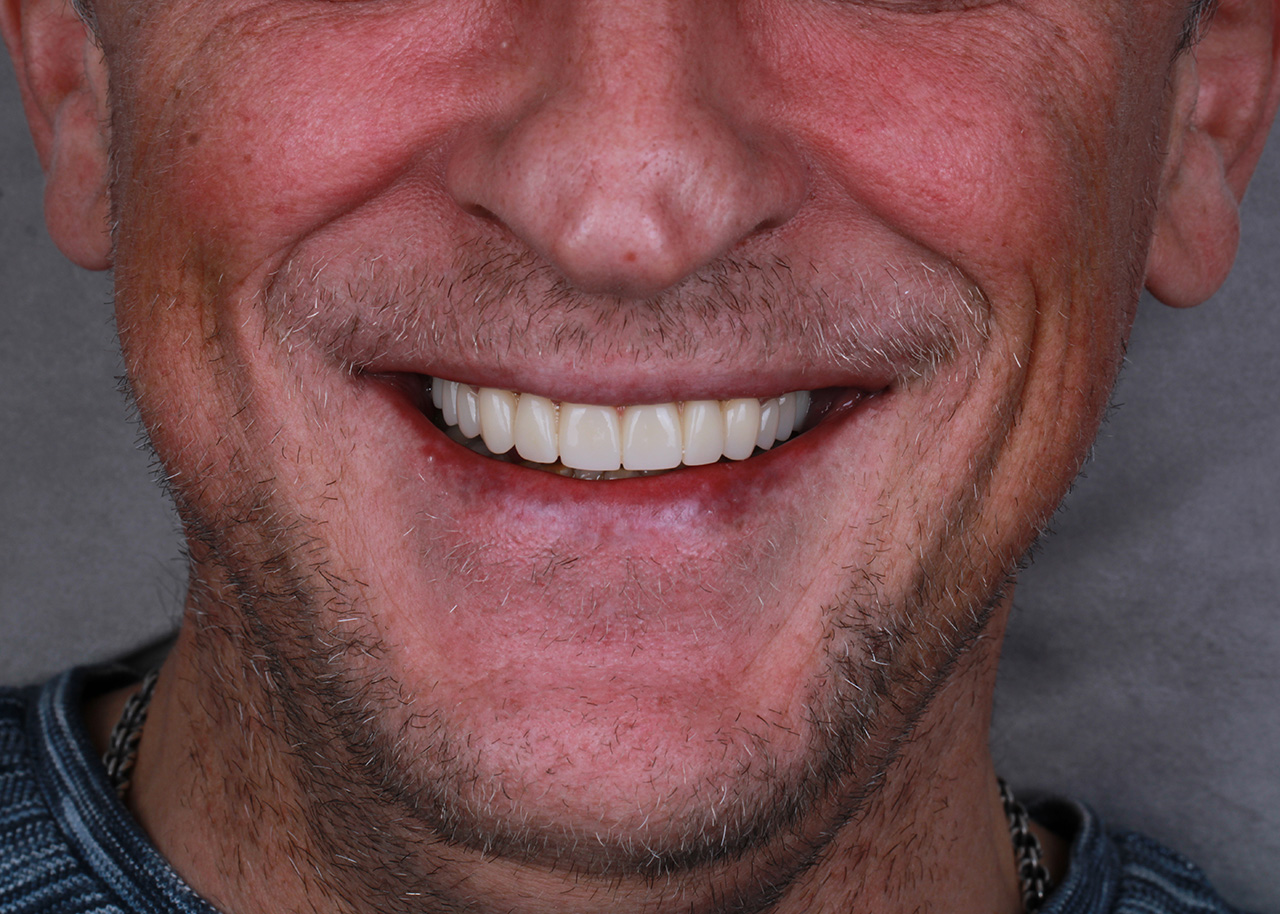

Восстановление зубов цирконием протезом после лечения

Проведена санация полости рта (удаление корней, лечение зубов) с последующей фиксацией циркониевых конструкций. Эстетика зубного ряда восстановлена.